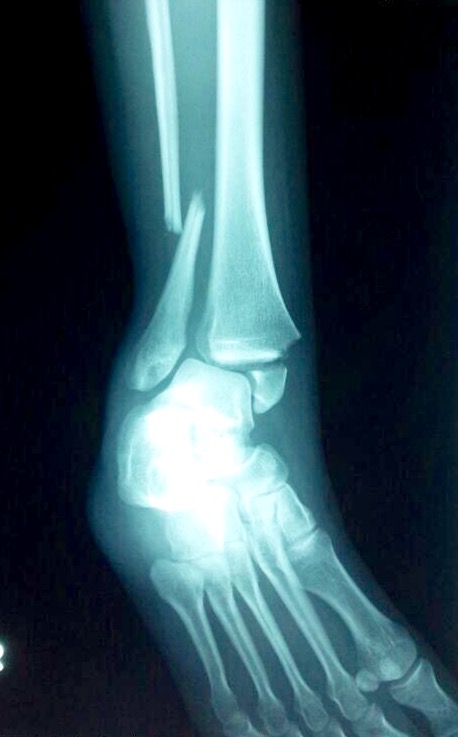

骨折

事故や外傷(転倒、交通事故など)、骨が弱くなる病気(骨粗鬆症、腫瘍、感染症など)など

痛み、腫れ、変形、機能障害など